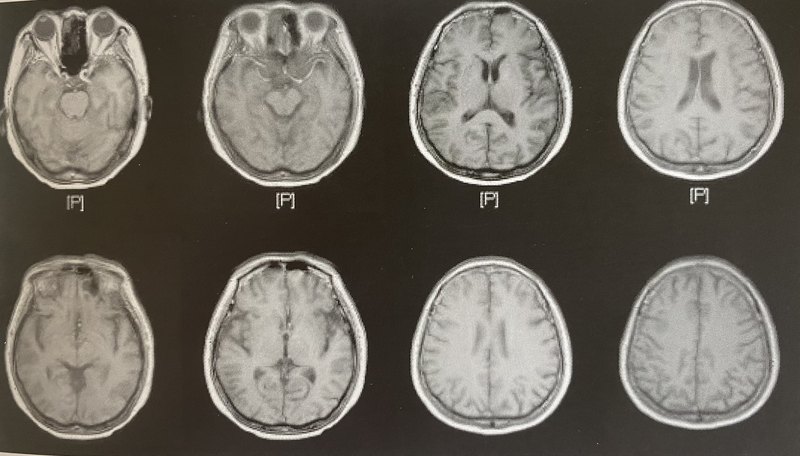

腦MRI(核磁)正常是否可以排除癡呆?

癡呆的腦核磁檢查對診斷非常有幫助,在癡呆不同階段、不同癡呆類型中核磁的影像學(xué)檢查是有區(qū)別的。如果腦核磁沒有非常明顯的異常是否可以排除癡呆?不可以。雖然絕大多數(shù)癡呆都會出現(xiàn)各種類型的核磁異常,但有一些類型癡呆在早期并沒有明顯核磁檢查異常,這種情況下需要進(jìn)行臨床癥狀,F(xiàn)18,腰穿等進(jìn)行綜合診斷和排除診斷,不能因?yàn)楹舜艣]有異常就排除這種早期的癡呆,比如下面這例DLB癡呆就是這種情況。